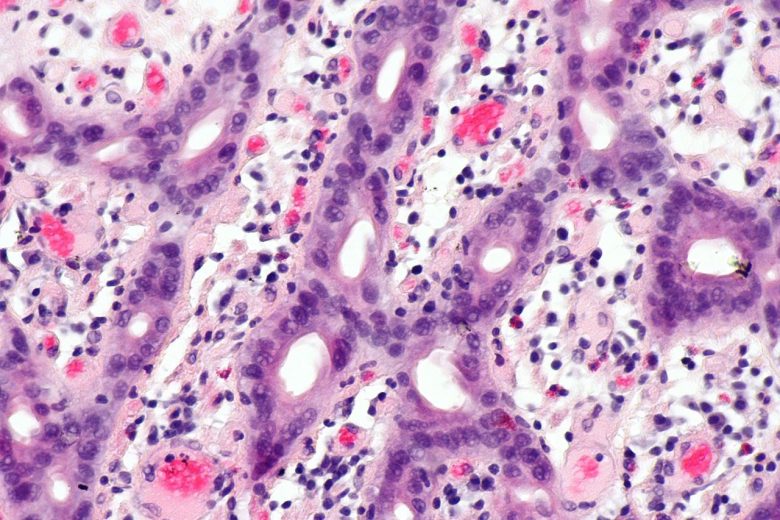

Pancreatic cancer

“Pancreatic cancer can develop from two kinds of cells in the pancreas: exocrine cells and neuroendocrine cells, such as islet cells. The exocrine type is more common and is usually found at an advanced stage. Pancreatic neuroendocrine tumors (islet cell tumors) are less common but have a better prognosis.”